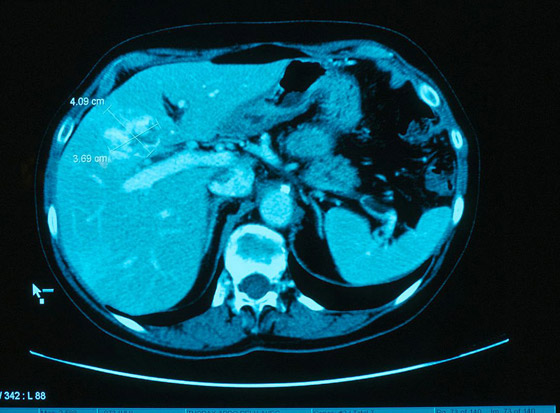

وليست الأسماك هي التي تسبب تطور السرطان. بدلاً من ذلك، فإن الديدان المفلطحة الطفيلية، أو الديدان المثقوبة الحية، هي التي تعيش بداخلها. فيما تتواجد الطفيليات في أسماك المياه العذبة في منطقة ميكونج. وقد أدى ذلك إلى إصابة "إيسان" بأكثر حالات سرطان الأقنية الصفراوية، أو سرطان القناة الصفراوية، في العالم. حيث يحب الكثير من الناس تناول طبق السمك النيئ.

كما يعمل أحد الأطباء في تايلاند، نارونج خونتيكيو، على محاولة حث عدد أقل من الناس على تناول هذه الأطعمة الشهية بعد فقدان والديه. وقال جراح الكبد نارونج خونتيكيو: "إنه عبء صحي كبير للغاية هنا. لكن لا أحد يعرف عن ذلك لأنهم يموتون بهدوء، مثل الأوراق المتساقطة من الشجرة". ويحمل هذا المرض، الذي أطلق عليه اسم "القاتل الصامت"، أحد أقل معدلات البقاء على قيد الحياة بين جميع أنواع السرطان إذا لم يتم علاجه بشكل عاجل.